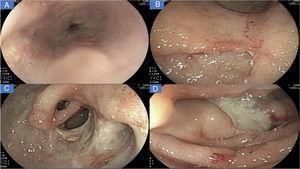

A new gastrointestinal endoscopy was performed that showed notching of Kerckring’s folds in the esophagus (Fig. 1A); multiple deep segmental ulcers with irregular edges in the stomach, with extensive involvement of the antrum and corpus (Fig. 1B-C); and severe segmental inflammatory changes in the duodenum, with greater compromise at the second part (Fig. 1D). Inflammatory disease was immediately suspected.

A) Linear ulcers, aphthous erosions, and notching of Kerckring’s folds in the esophagus. B) Severe inflammatory changes that affect the mucosa of the corpus, with signs of erythema, edema, nodularity, and deep, segmental ulcers. C) View of the gastric antrum, showing a deep ulcer affecting more than 70% of the circumference, with punched-out areas, pyloric deformity, and mucosal bridging (black arrow). D) Severe inflammatory changes in the duodenum, with serpiginous ulcers and a fibrin-covered dominant ulcer in DII.